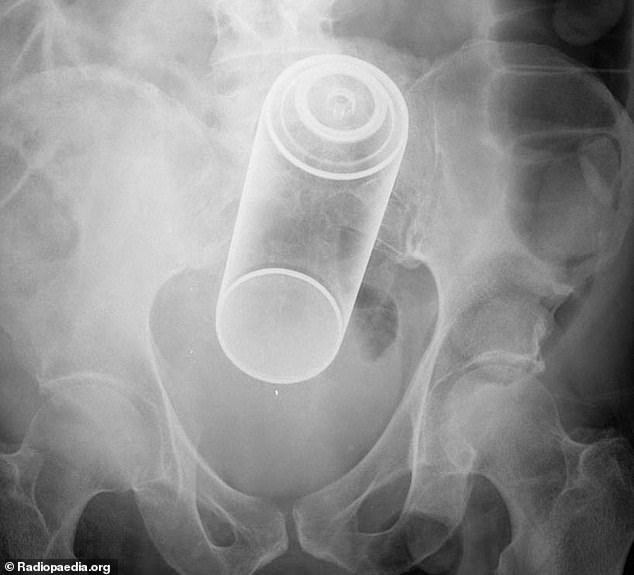

1. Ένα μπουκάλι Αεροζόλ…